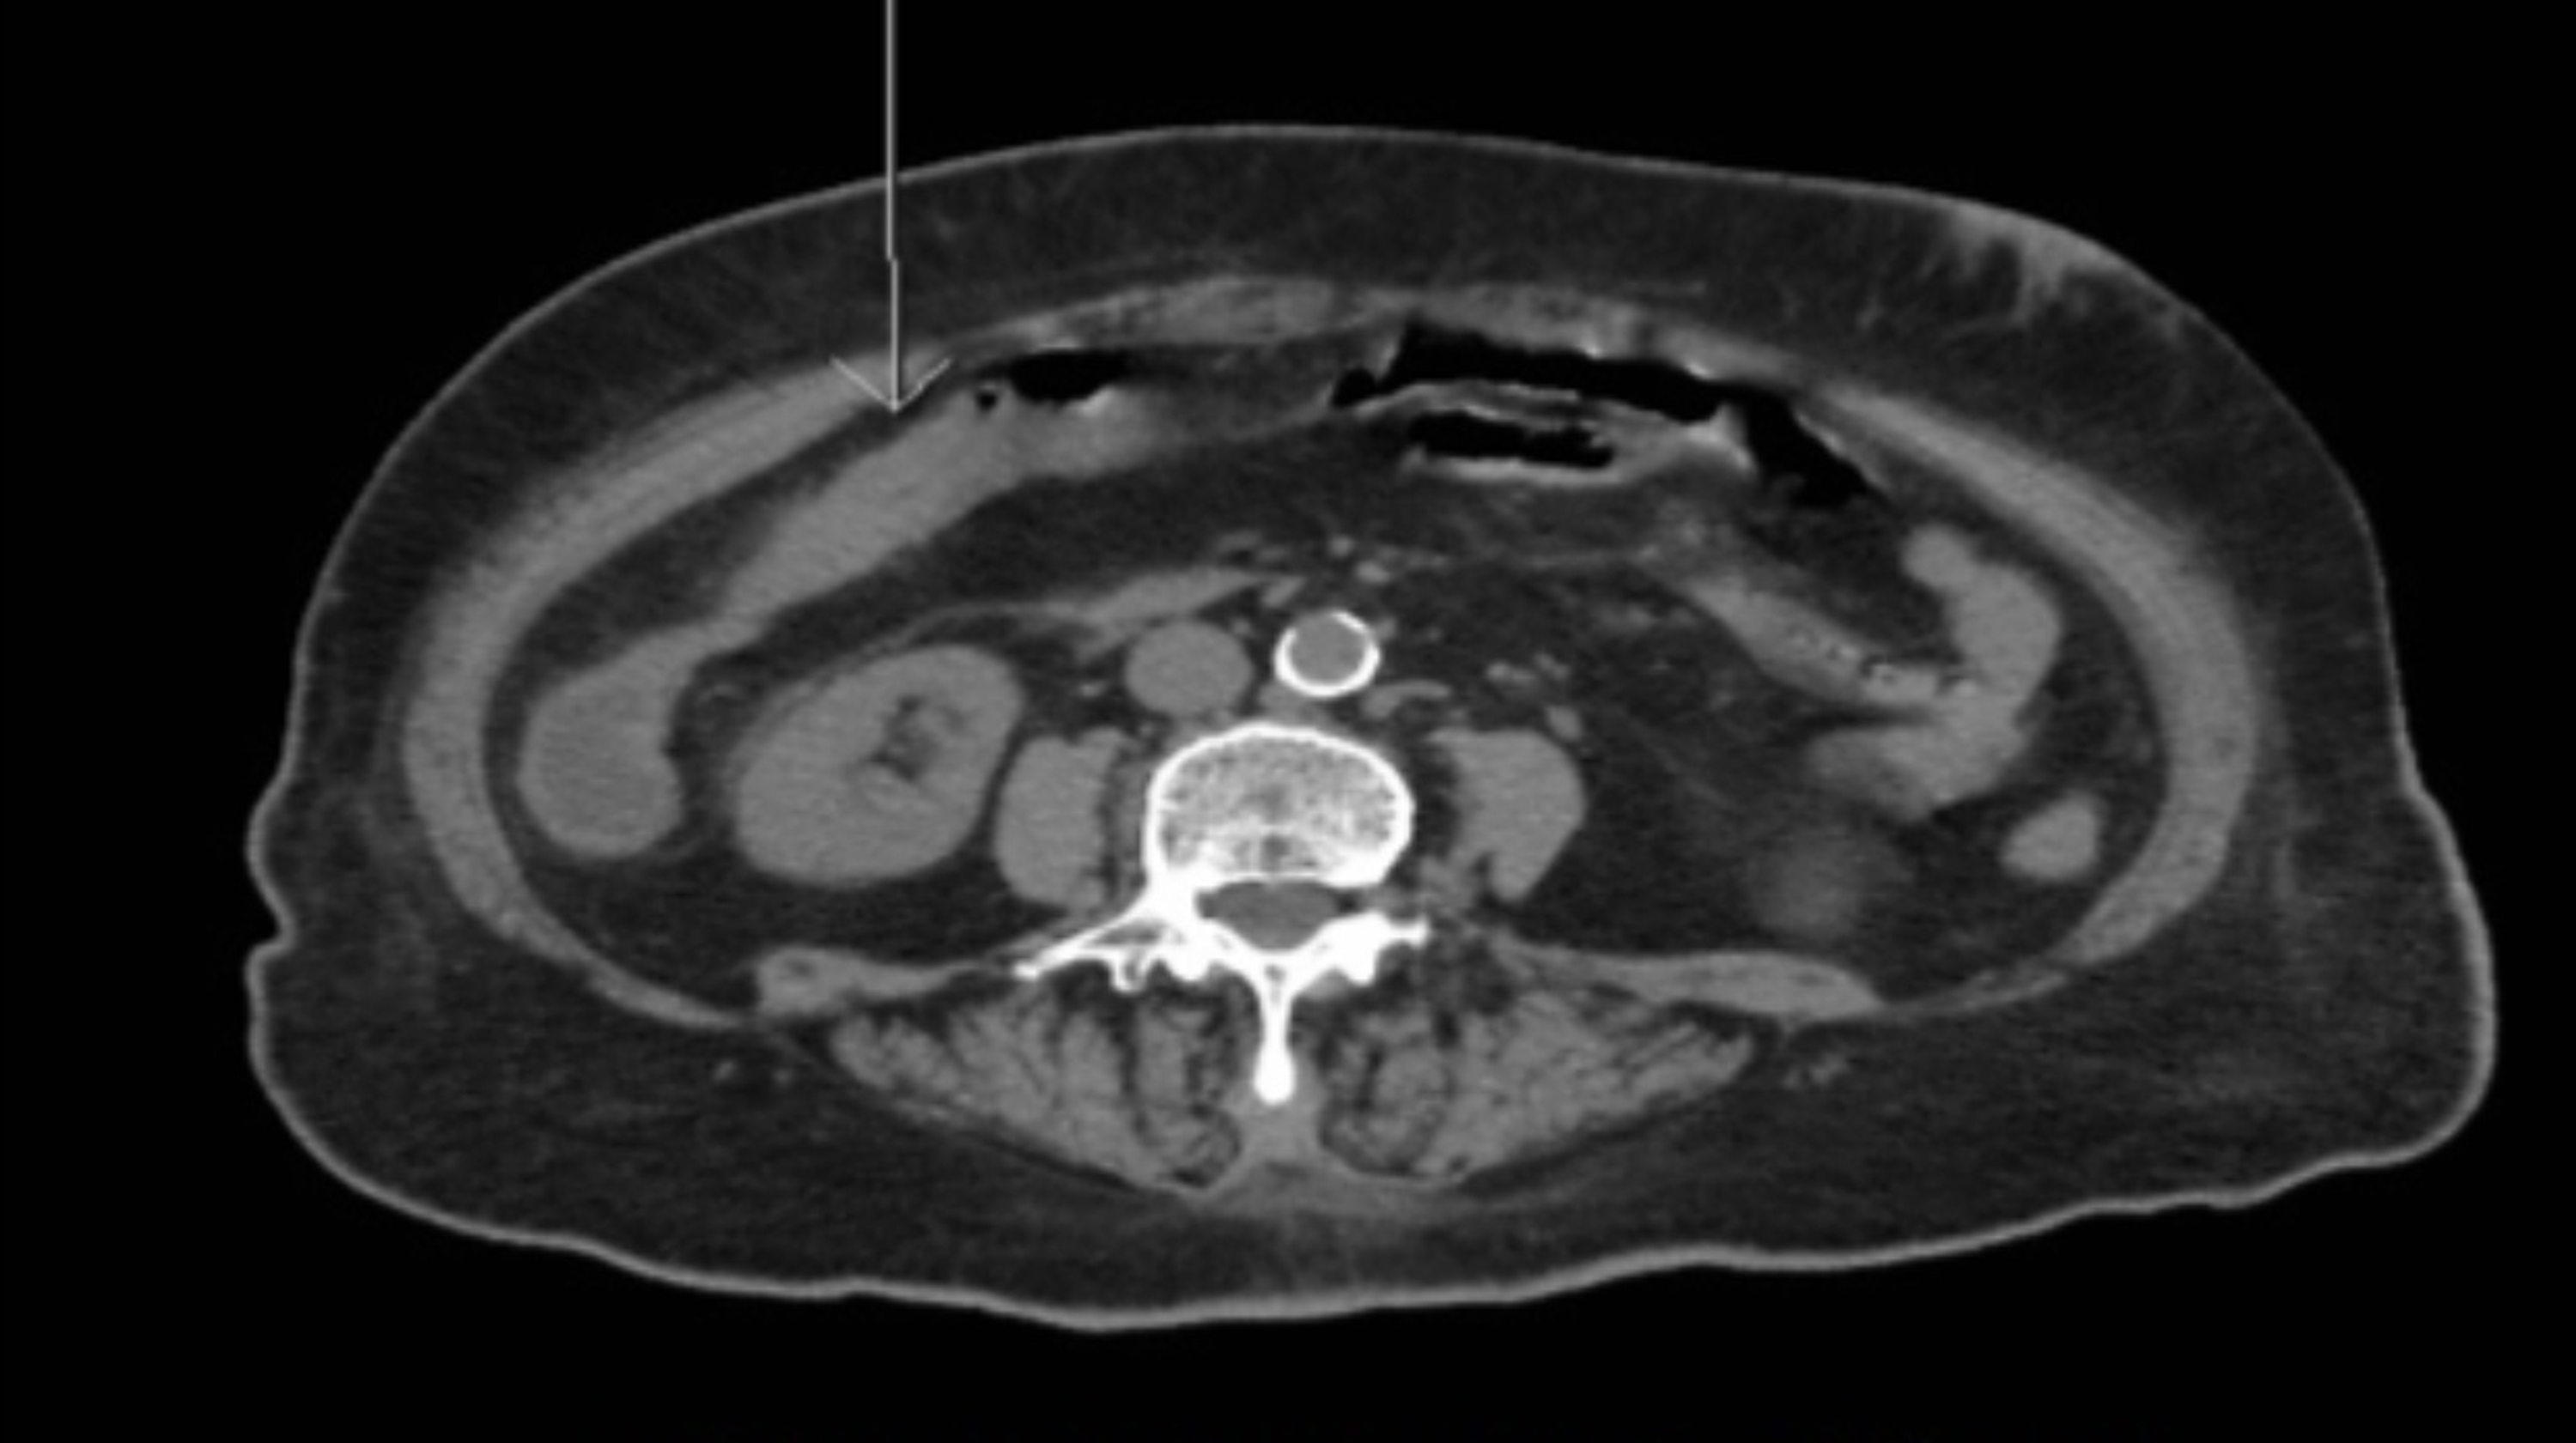

From radiopaedia.org

Large bowel watershed ischemia Image Ischemic Colitis Watershed Areas These watershed areas are most vulnerable to ischemia when blood flow decreases, as they have the fewest vascular collaterals. Watershed areas correspond to the splenic flexure, also known as griffith's point, and sigmoid colon, or sudeck's. The colon venous drainage is the parallel of arterial supply. Watershed areas account for about 70% of ischemic colitis cases. Watershed zones are areas. Ischemic Colitis Watershed Areas.